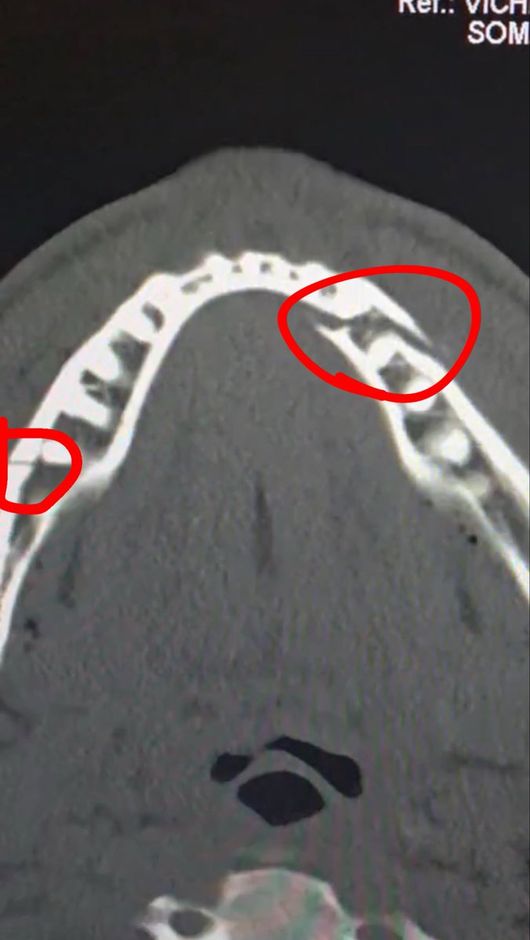

실제로 폴의 부상은 결코 가볍지 않았다. 진단 결과 그의 턱뼈는 두 곳이나 골절돼 세 동강이 난 모습이었다. 그는 곧바로 수술대에 올랐고, 티타늄 플레이트 두 개를 삽입했다. 치아도 일부 제거해 한동안 정상적인 식사도 불가능한 것으로 알려졌다.

폴은 소셜 미디어를 통해 자신의 수술 후 상태를 공개하면서 "통증이 심하지만 난 괜찮다. 턱뼈가 두 군데나 으스러졌다. 7일 동안 유동식을 먹어야 한다"라고 밝혔다. 경기를 앞두고 조슈아에게 "널 죽여버리겠다"라고 도발했던 폴이지만, 조슈아의 벽은 너무나 높았다.